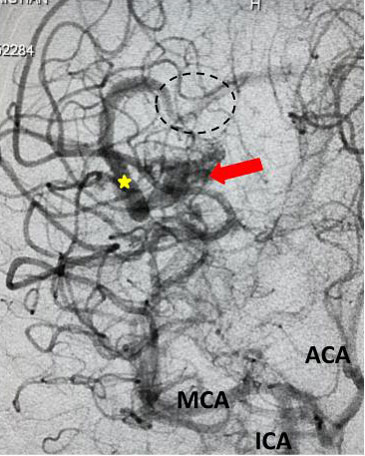

The patient was taken to the angio-suite where an angiogram confirmed a high flow, high pressure AVM fed primarily by the posterior cerebral artery with a small collateral from the middle cerebral artery (Fig 2 and 3). The AVM drained into a tortuous, partially occluded and stenotic single draining vein.

Fig 3. Lateral view, late-arterial phase of a right internal carotid artery (ICA) injection. Filling of the AMV (red arrow) by the fetal posterior cerebral artery (PCA) and small middle cerebral artery feeder (blue arrow). The large tortuous draining vein (yellow star) with venous stenosis and the suggestion of clot (dotted circle) can be seen.